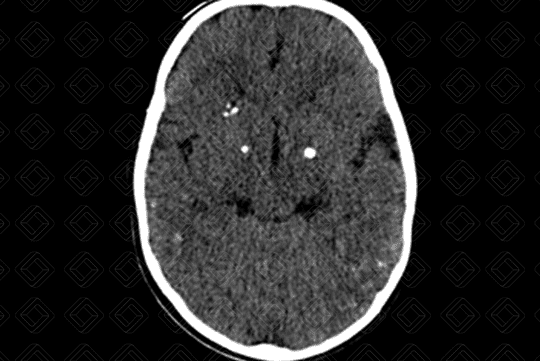

• Achados de imagem neurológicos: O rastreio inicia-se com ultrassonografia transfontanelar. Diante da gravidade das lesões e para avaliar a extensão das calcificações, pode ser realizada adicionalmente, tomografia computadorizada do crânio e até mesmo, ressonância magnética . Calcificações puntiformes periventriculares (subependimárias) são características, microcefalia (depende do momento da infecção fetal - as que ocorrem no período gestacional mais precoce são mais graves), distúrbios de migração neuronal e hipoplasia cerebelar.